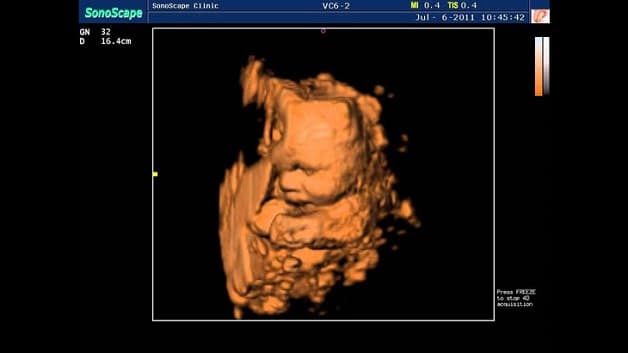

Siêu âm Doppler là kĩ thuật khá phổ biến hiện nay khi được áp dụng rộng rãi tại nhiều bệnh viện, phòng khám khác nhau, bởi đặc tính mang lại kết quả chính xác cao. Siêu âm doppler thai nhi là kĩ thuật siêu âm sử dụng sóng cao tần để đo nhịp tim, mạch máu và các bộ phận khác của cơ thể. Một trong những điểm vượt trội của kỹ thuật siêu âm này so với siêu âm truyền thống là việc kiểm tra được dòng chảy của máu trong động mạch, tĩnh mạch. Từ đây bác sĩ dễ dàng đánh giá tình trạng sức khỏe trong quá trình phát triển của thai nhi.

Cụ thể, nhờ siêu âm doppler màu, tình trạng hở van 2 lá hay 3 lá của tim thai sẽ được phát hiện nhanh chóng. Trường hợp hẹp van tim cũng sớm được nhận biết thông qua việc đo vận tốc dòng máu qua van động mạch chủ, động mạch phổi.

Siêu âm doppler thai thường được các bác sĩ sử dụng trong những tháng cuối thai kỳ